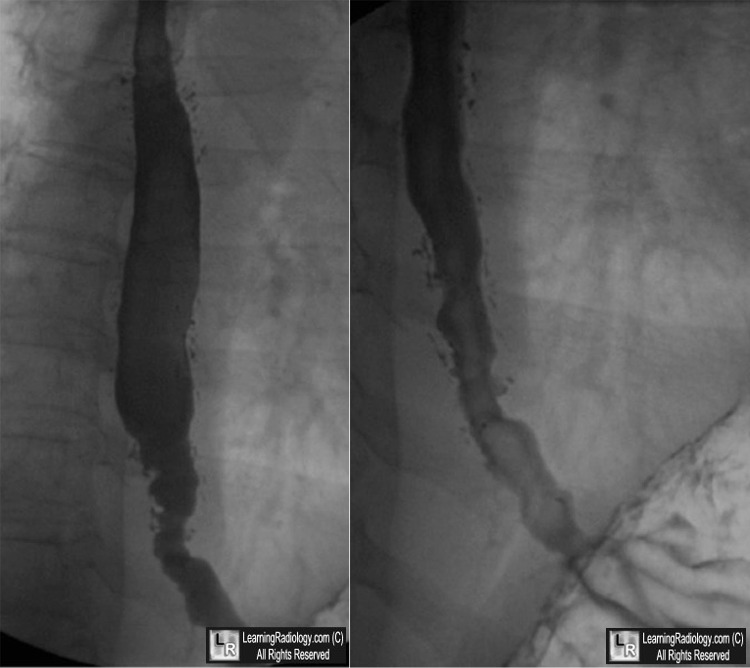

Intramural Pseudodiverticulosis. Two images from a barium esophagram show innumerable,

small outpouchings of barium extending from the lumen into the wall. (white ovals)

There are also linear collections indicating intramural tracking.